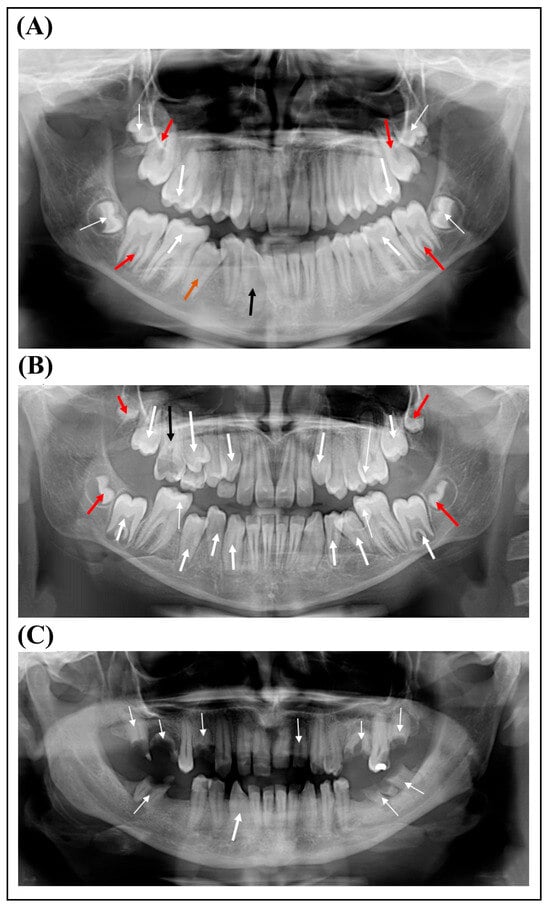

1. Introduction

2. Case Presentation